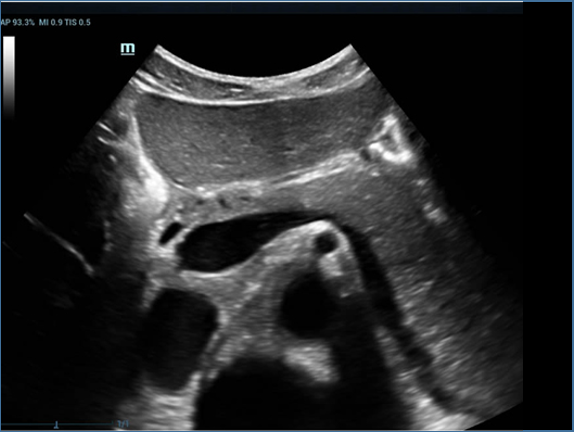

Mindray, ?irketin kuruldu?u gĂŒnden bu yana sĂŒrekli olarak tan?sal do?rulu?u iyile?tirmeye ?al??maktad?r. Devrim niteli?indeki ZONE Sonography? Teknolojisi ile desteklenen Resona 7ânin yeni ZST+ platformu, b?lge g?rĂŒntĂŒsĂŒ alma ve kanal veri i?leme ?zellikleri ile ultrason g?rĂŒntĂŒsĂŒ kalitesini daha ĂŒst bir dĂŒzeye ??kar?yor.

Resona 7, ĂŒstĂŒn dĂŒzeyde g?rĂŒntĂŒ kalitesine ek olarak, vaskĂŒler hemodinamik de?erlendirmesi i?in devrim niteli?indeki V Ak??? ile fetĂŒs CNS tan?lamas? i?in 3 boyutlu veri kĂŒmesinden dĂŒzlem g?rĂŒntĂŒsĂŒ alma konusunda en iyi birime sahip oldu?undan, klinik ara?t?rma yeterliklerini de art?rmaktad?r. En sezgisel, harekete dayal? ?oklu dokunmatik i?letim ile tĂŒm temel klinik ?zellikleri bir araya getiren Resona 7, ultrason yenili?i konusunda ger?ek anlamda yeni dalgalara ?ncĂŒlĂŒk ediyor.